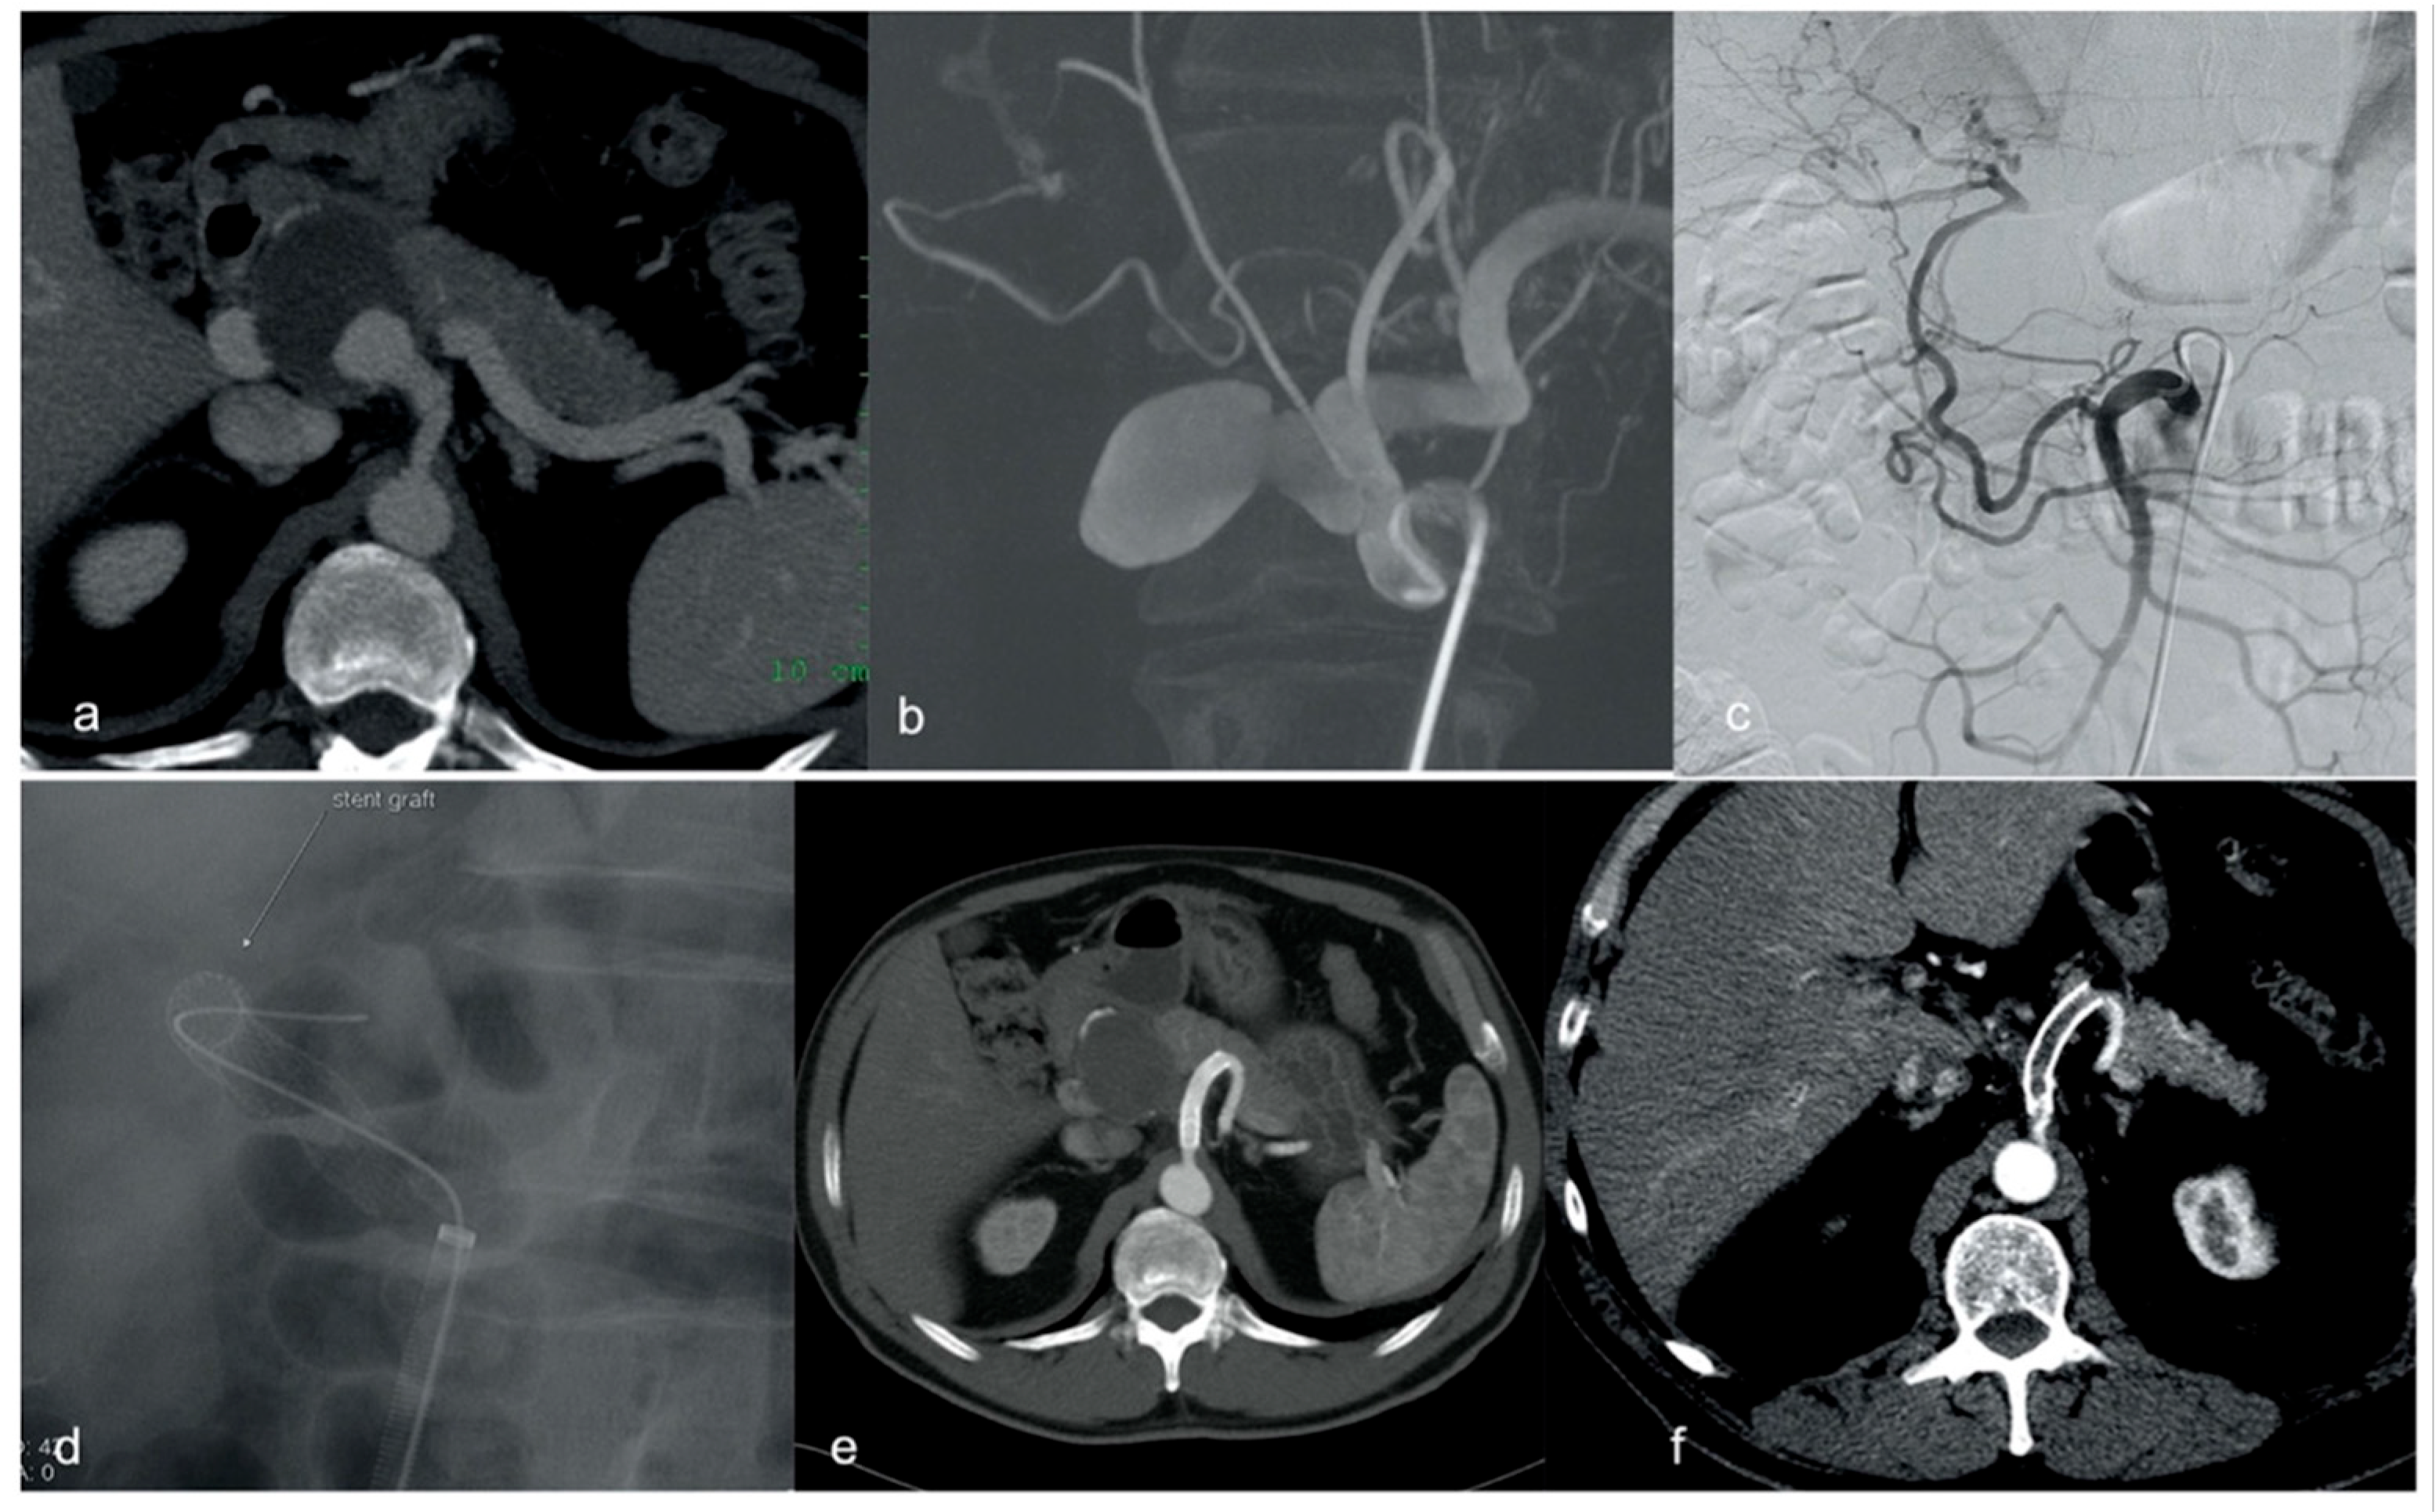

| 4 | Male | 27 | VAA | Renal | Elective | 25 | Jostent 5 × 19 mm |

| 4 | Jostent 5 × 19 mm | 90 | Yes | - | - |